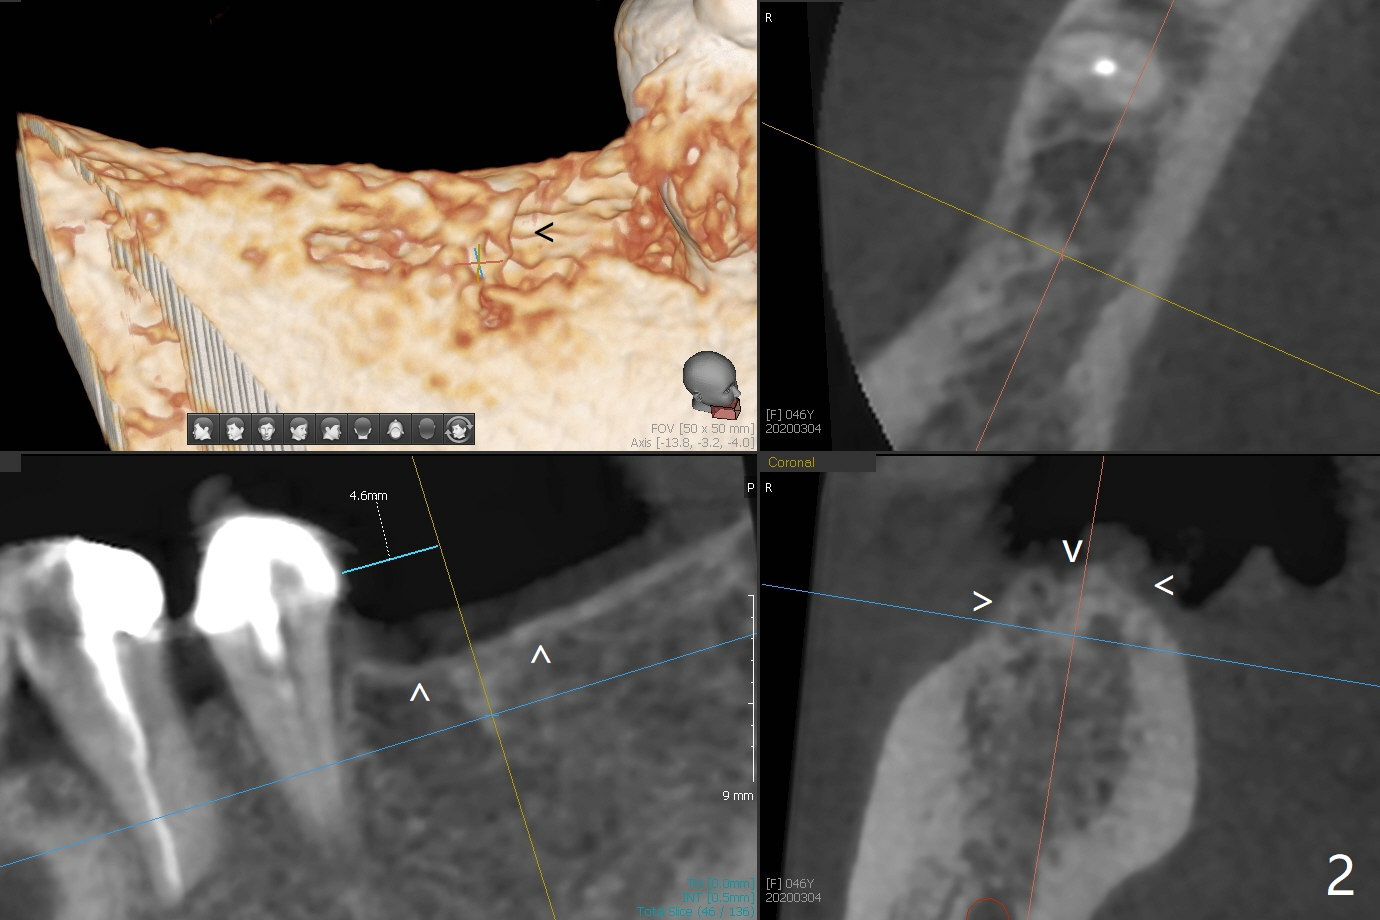

A 46-year-old woman returns for preparation for an implant at #30 two years 3 months post #6 (M) and 7 implant crown cementation (Fig.1). With the moderate ridge, implant placement should be easy, but the vertical restorative height is limited due to the opposing supraerupted molar. If the keratinized gingiva is narrow, make incision instead of tissue punch. In fact the crestal cortex is the most important structure associated with implant placement and should be carefully studied prior to implant design (Fig.2 arrowheads in 3D view as well as the sagittal and coronal (Fig.3) sections). If socket preservation were done, the ridge would be wider and taller (Fig.4 yellow dashed line) with possible thicker cortical bone.